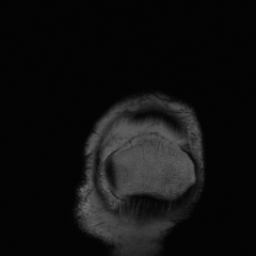

5.3 Out-of-Domain Generalisation

One way to test the generalization capability of the trained X-Diffusion is to test it on a completely different domain from an MRI dataset not seen during training. We report the single-slice results on NYU fastMRI [37, 82], a knee MRI dataset, using the X-Diffusion trained on the BRATS brain MRIs. The results are shown in Figure 9 and Table 2. It shows how successfully X-Diffusion is able to generate knee MRIs from a single image, despite not seeing knees at all in training. To qualitatively assess how realistic our generated 3D volumes were (produced from a single slice), we gave 20 generated examples alongside their real MRI counterparts to an expert orthopaedic surgeon. He was then asked to identify the real example from a given pair. The surgeon identified with certainty only 10 real knee MRIs out of 17, while could not decide on the remaining 3 of the 20 MRI pairs. This further validates the generated out-of-domain MRIs.